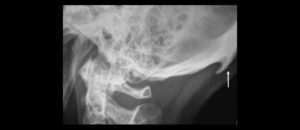

228 – Impacto de la CBCT en la toma de decisión del tratamiento relacionado a extracción de terceros molares impactados.

El objetivo del presente estudio fue evaluar los factores (referidos a la CBCT) que influyen en la toma de decisión en tratamientos para extracción de